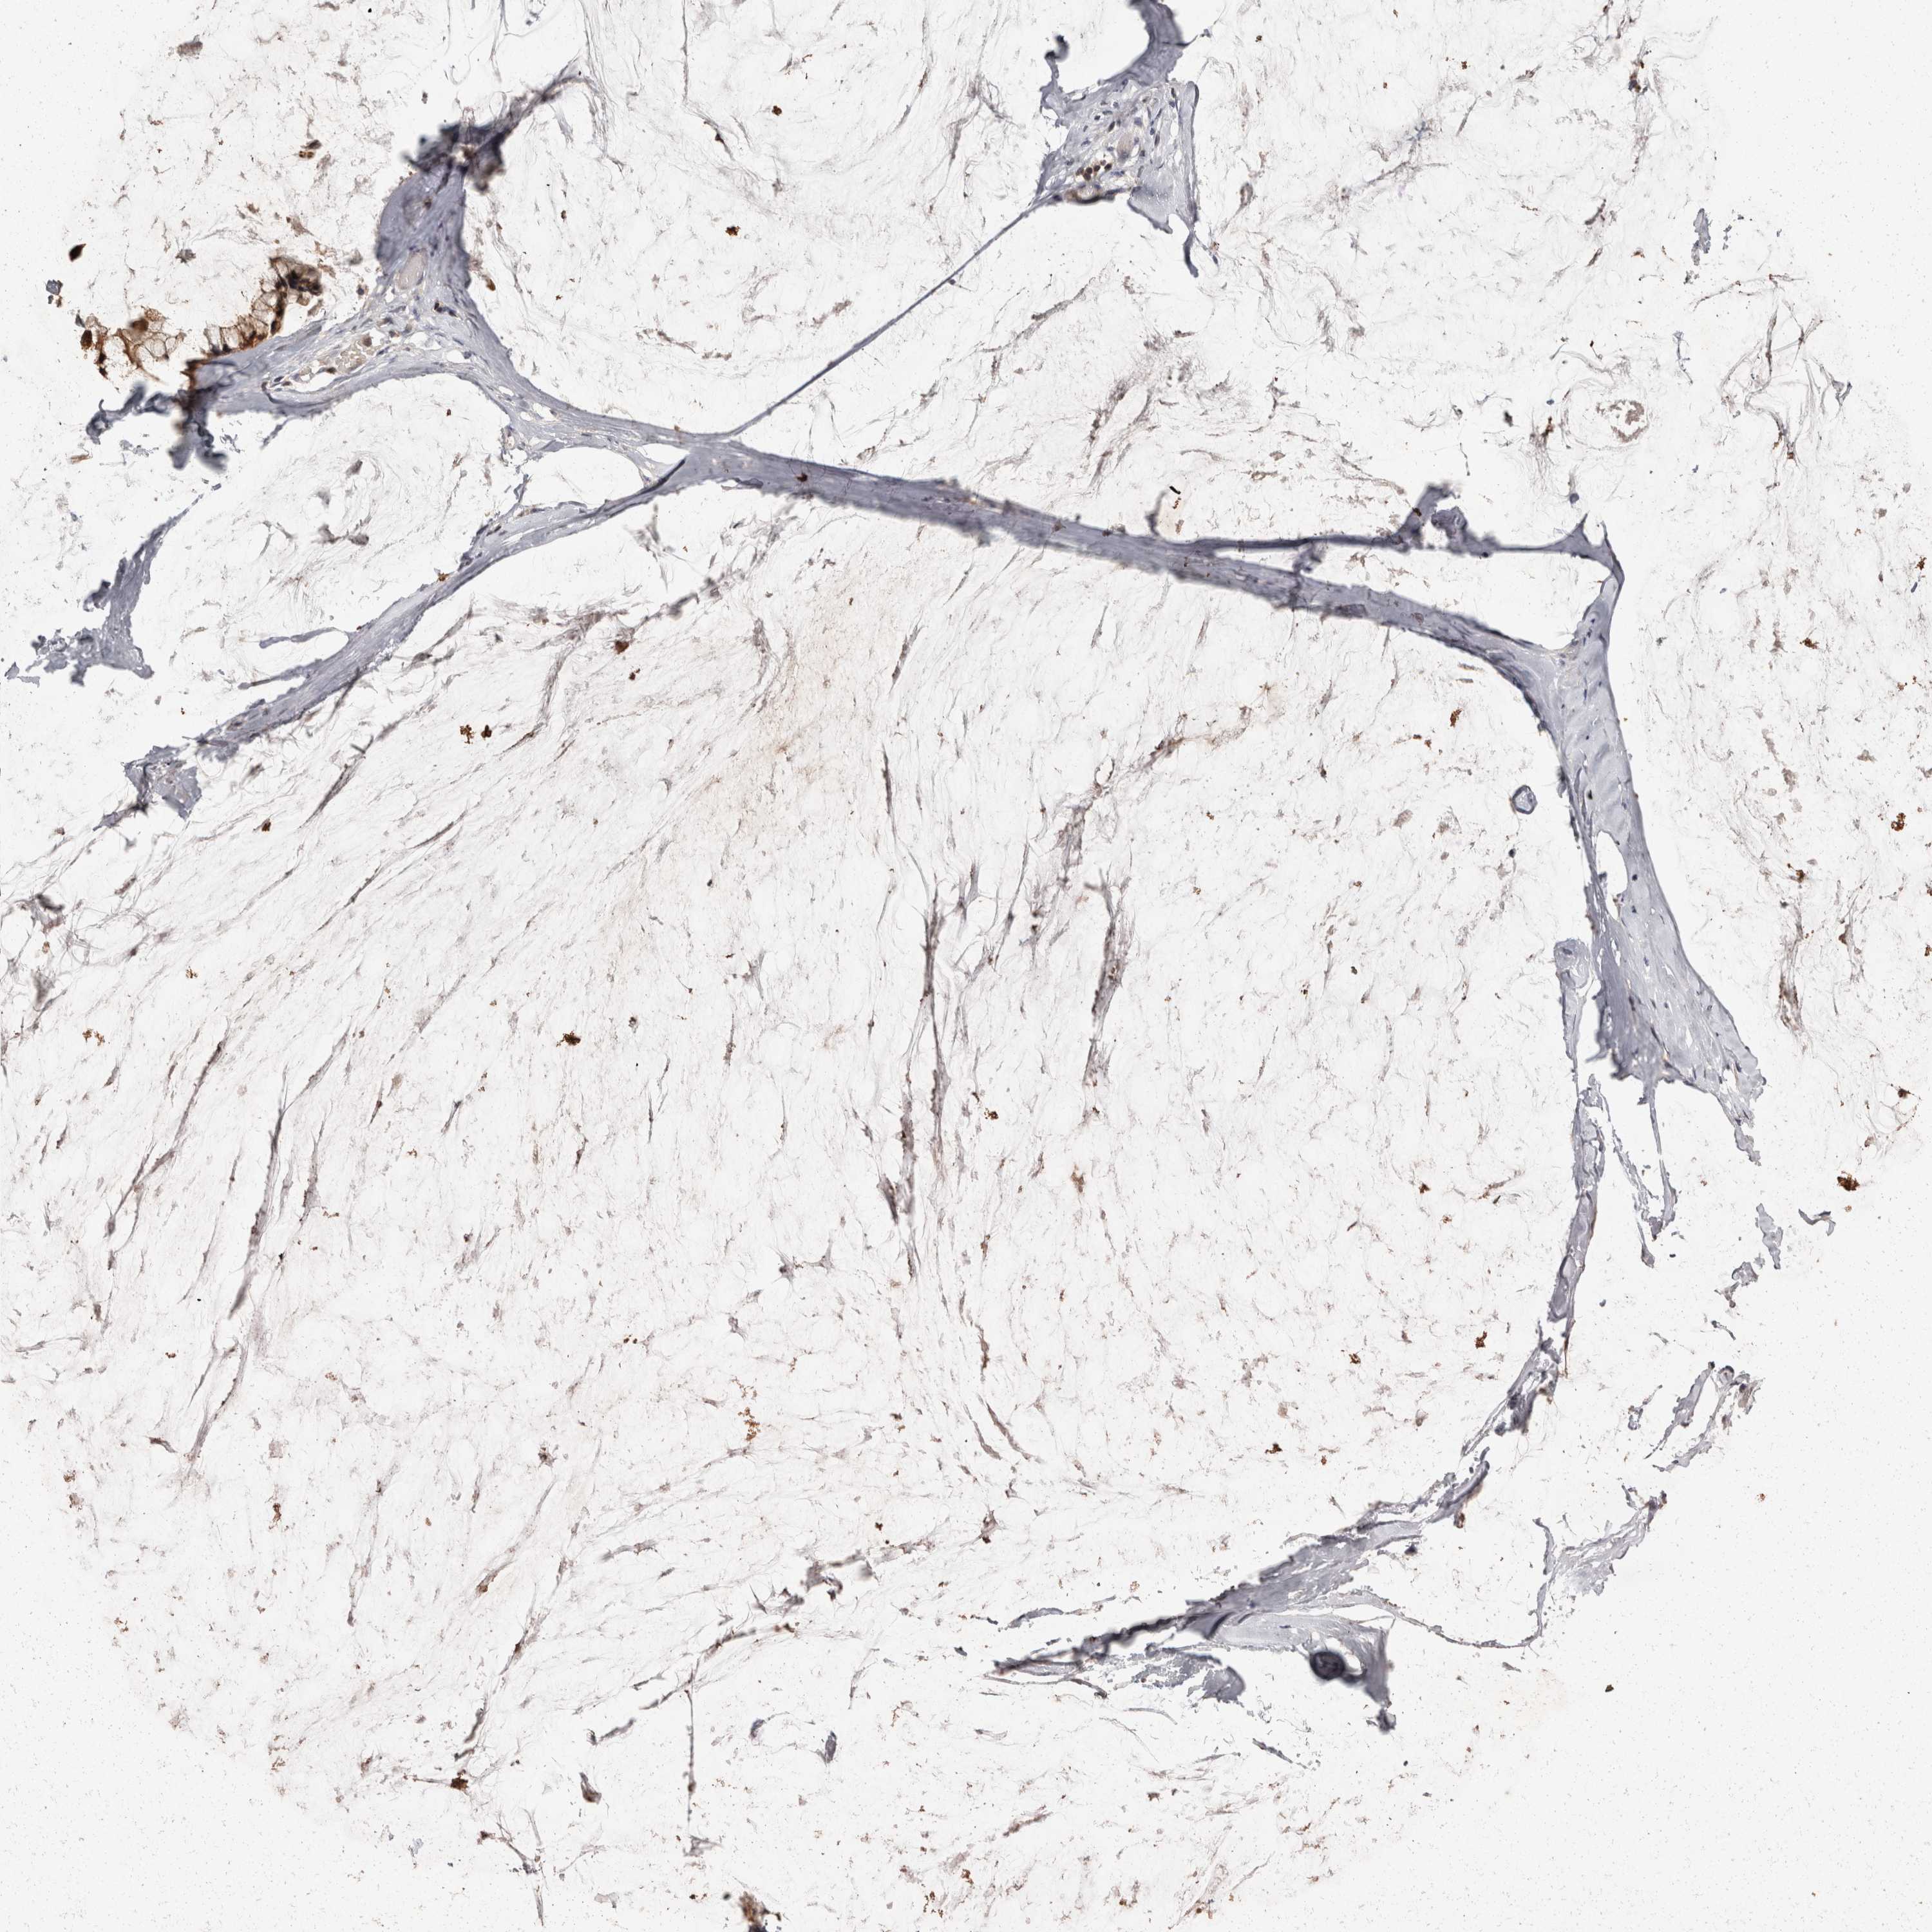

OVARIAN CANCER - Protein expressioni

A mouse-over function shows sample information and annotation data. Click on an image to view it in a full screen mode. Samples can be filtered based on level of antibody staining by selecting one or several of the following categories: high, medium, low and not detected. The assay and annotation is described here.

Note that samples used for immunohistochemistry by the Human Protein Atlas do not correspond to samples in the TCGA dataset.

Antibody stainingi

Antibody staining in the annotated cell types in the current human tissue is reported as not detected, low, medium, or high, based on conventional immunohistochemistry profiling in selected tissues. This score is based on the combination of the staining intensity and fraction of stained cells.

Each image is clickable and will lead to virtual microscopy that enables deeper exploration of all samples and also displays staining intensity scores, fraction scores and subcellular localization as well as patient and tissue information for each sample.

Carcinoma, endometroid

Cystadenocarcinoma, mucinous, NOS

Carcinoma, NOS